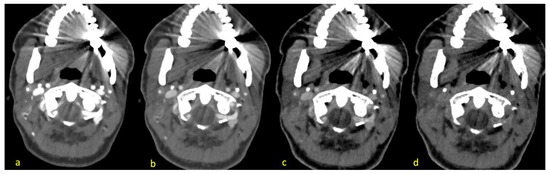

3.2. Hyperattenuation Artifacts

3.3. Hypoattenuation Artifacts

3.4. Artifacts and Noise in Muscle

3.5. Artifacts and Noise in Vessels